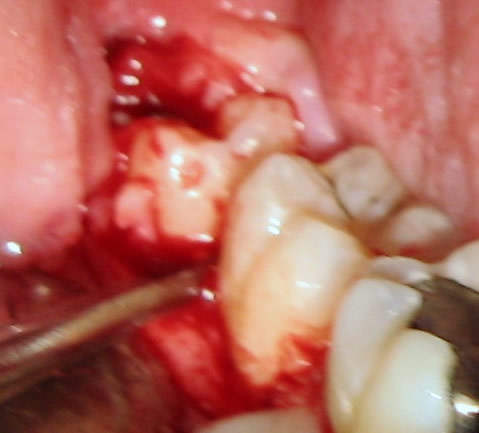

Δεν υπάρχει συμφωνία στη βιβλιογραφία σχετικά με τον κίνδυνο περιοδοντικής βλάβης του κάτω δεύτερου γομφίου μετά από την αφαίρεση του εγκλείστου φρονιμίτη. Ο εργασίες που αξιολογούν ακτινογραφικά και κλινικά τις περιοδοντικές βλάβες άπω του δεύτερου γομφίου (βάθος θυλάκων, επίπεδο πρόσφυσης, οστική απώλεια), καταλήγουν σε διαφορετικά ευρήματα τεκμηριώνοντας έτσι την αβεβαιότητα και τη μη προβλεψιμότητα σε αυτήν την πιθανή επιπλοκή.

Άλλες εργασίες καταλήγουν ότι αυτές οι βλάβες δεν είναι κλινικά σημαντικές (Richardson DT. και Dodson TB. 2005) και ότι βελτιώνονται σημαντικά μέσα στον πρώτο μετεγχειρητικό χρόνο (Montero J. και Mazzaglia G. 2011) ή και ότι οδηγούν σε αύξηση του οστού (Krausz AA. κσ. 2005) και άλλες ότι αυτές οι βλάβες μπορεί να είναι σημαντικές και να συσχετίζονται με την εγγύς απόκλιση του εγκλείστου, την ακτινογραφική παρουσία ακτινοδιαυγαστικής αλλοίωσης στην περιοχή, με την στοματική υγιεινή αλλά και την ηλικία (Kan KW. κσ. 2002, Kugelberg CF. 1990).

Ωστόσο υπάρχει συμφωνία στο ότι η επιλογή χειρουργικού κρημνού (τύπου φακέλου, τριγώνου ή άλλων τροποποιημένων) δεν μπορεί να επηρεάσει την τελική μορφή της ενδεχόμενης περιοδοντικής βλάβης. Αναφέρεται ότι μπορεί να επηρεάσει θετικά στο αρχικό μετεγχειρητικό διάστημα (Kirtiloğlu T. κσ. 2007) αλλά όχι και στην τελική έκβαση, ένα χρόνο και περισσότερο μετά την αφαίρεση του εγκλείστου (Briguglio F. κσ. 2011, Chaves AJ κσ. 2008, Karaca I. κσ. 2007, Quee TA. κσ. 1985). Έχει περιγραφεί και προληπτική προεγχειρητική ορθοδοντική μετακίνηση του εγκλείστου ώστε να μετατραπεί η εξαγωγή του σε μη χειρουργική (Hirsch A. κσ. 2003).

Είναι προφανές ότι θα χρειαστούν και άλλες μελέτες, κυρίως προοπτικές και με περισσότερες περιπτώσεις, τόσο για να εξεταστούν οι παράγοντες που συμβάλλουν στη εμφάνιση αυτής της επιπλοκής όσο και για την πρακτική της αντιμετώπιση. Για παράδειγμα, ο παράγοντας «χειρουργικοί χειρισμοί» – και ανεξαρτήτως επιλεγόμενου κρημνού – θα πρέπει επίσης να αξιολογηθεί. Τόσο από την πλευρά της έκτασης και του βάθους της επέμβασης που ενίοτε θα απαιτηθούν για την ασφαλή χειρουργική του εγκλείστου όσο και από την πλευρά της εμπειρίας.